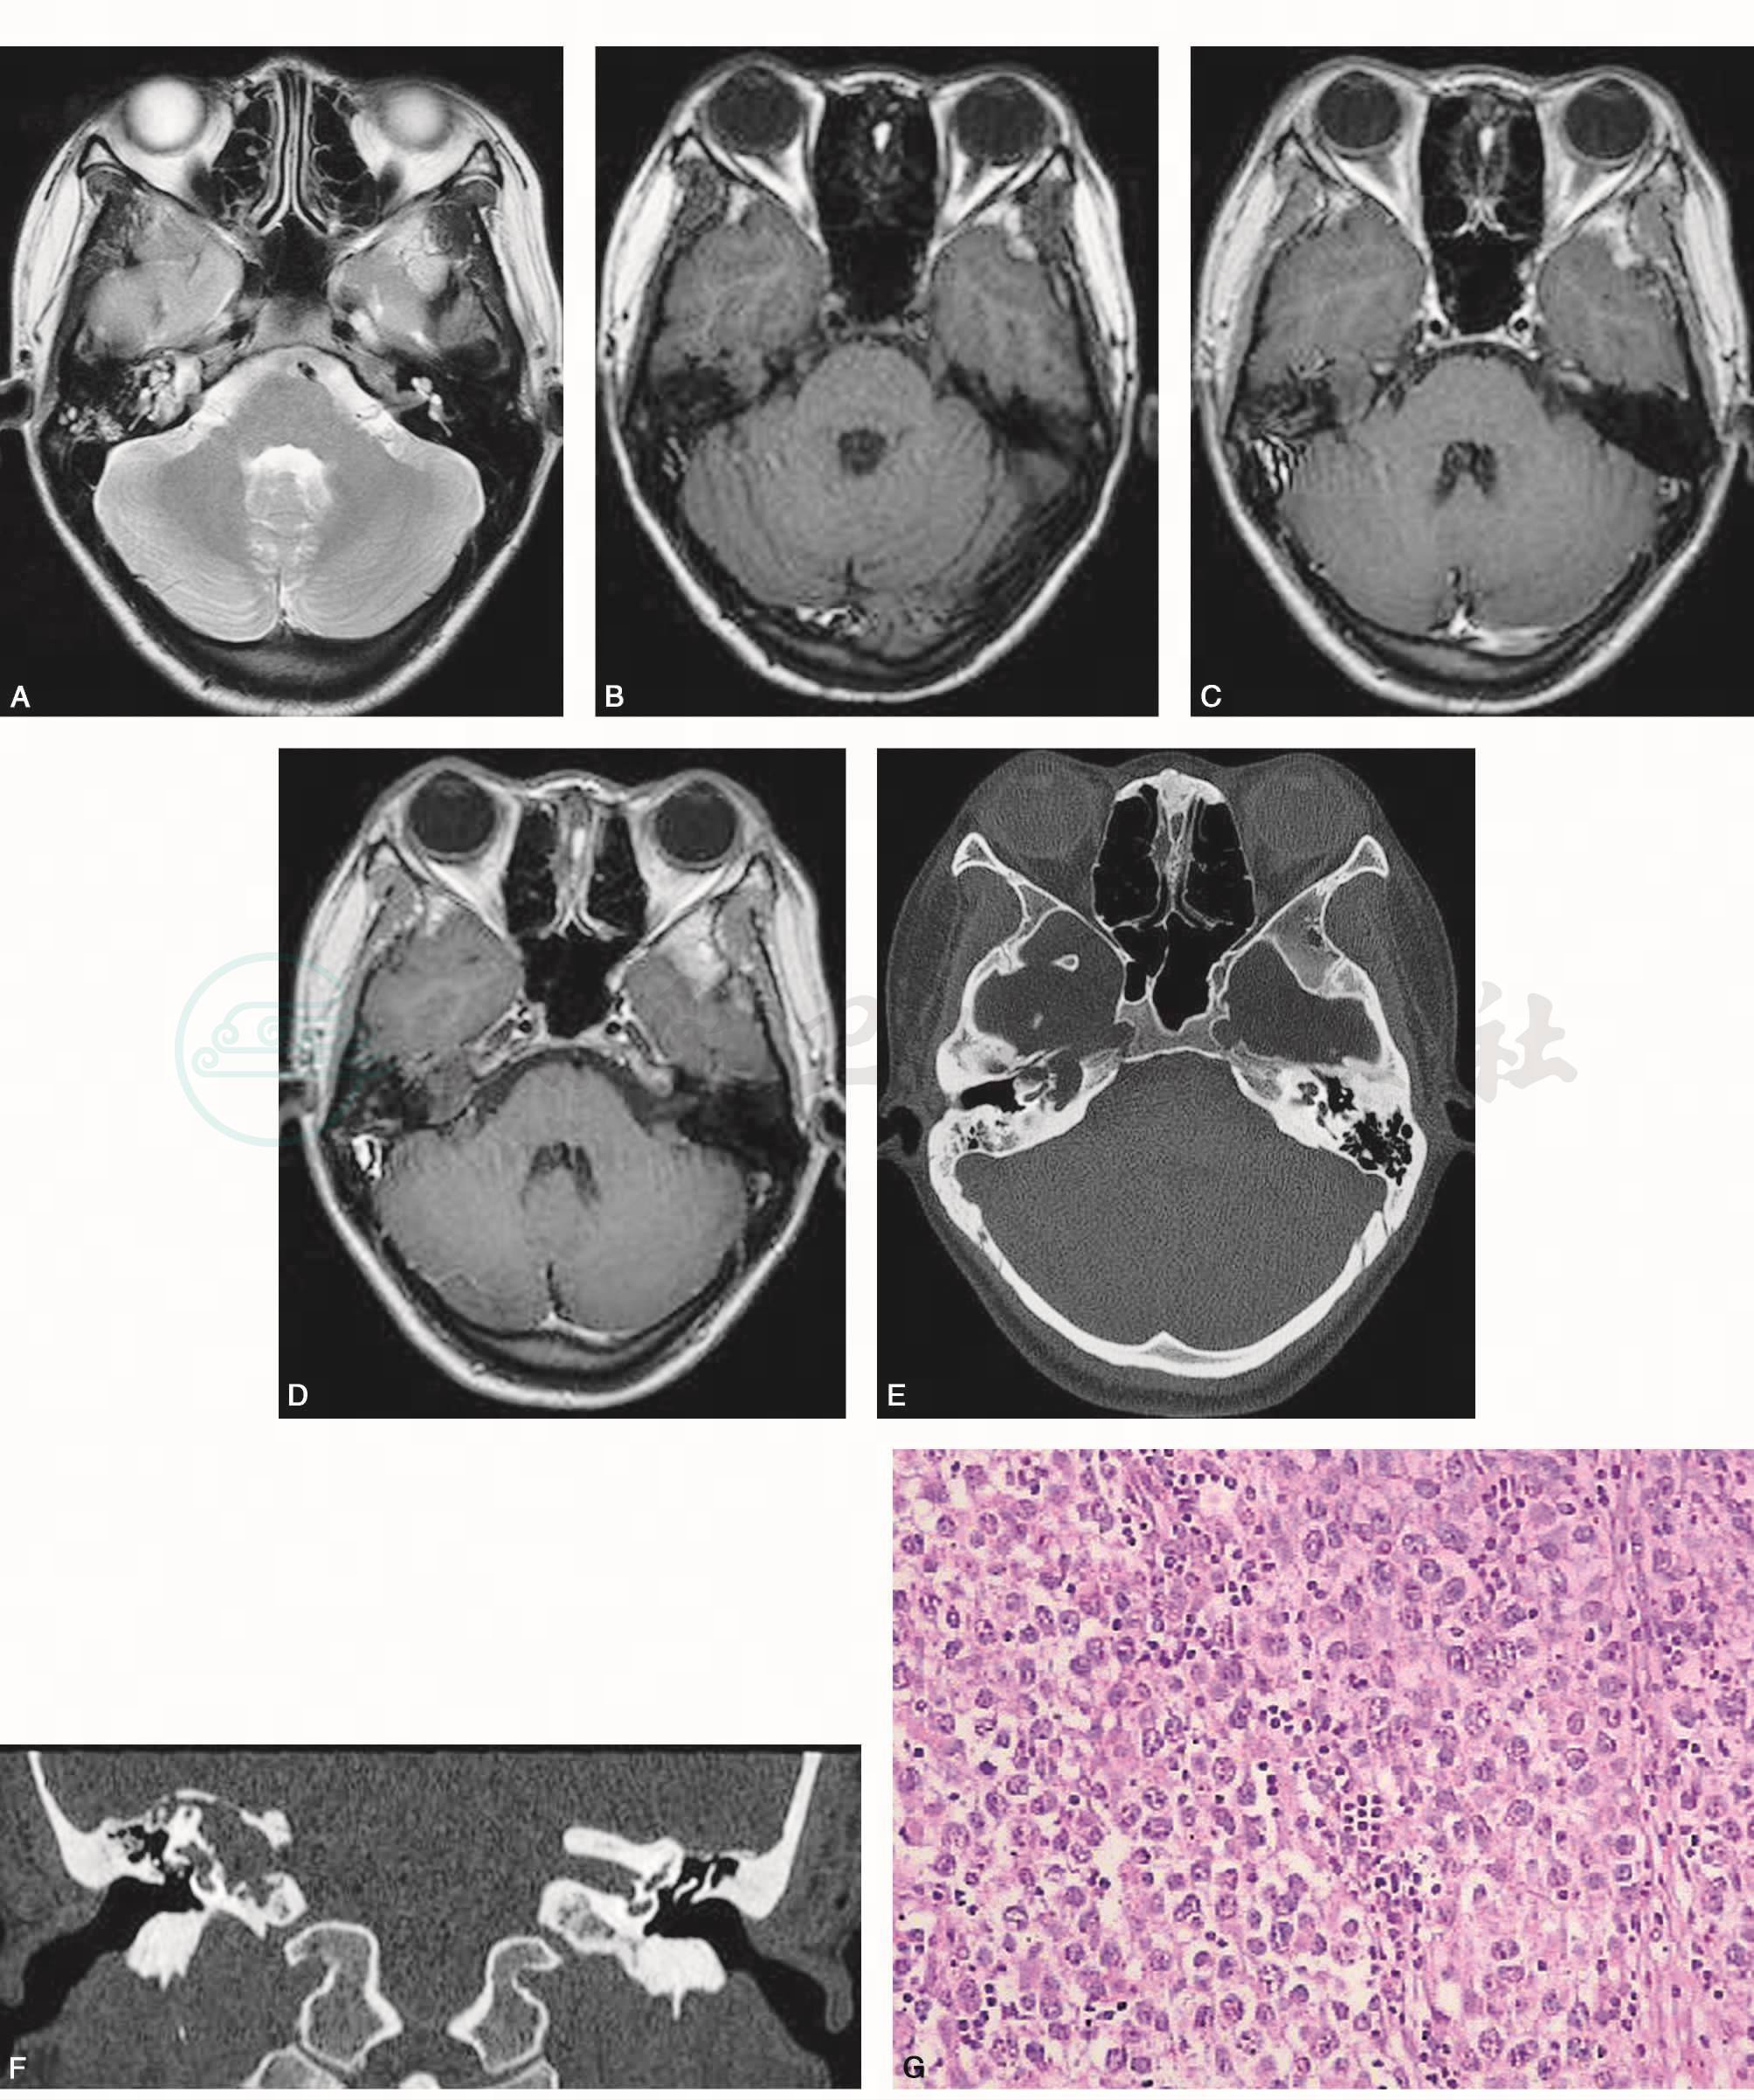

于右侧岩骨尖见一不规则结节灶,约2.0cm×1.5cm,T2WI为稍高信号(图1A),T1WI为等信号,其信号稍欠均匀,病灶周边信号稍高(图1B),增强后强化不明显(图1C、D)。CT见右侧耳蜗、岩骨尖、听神经管区见骨质破坏,部分边缘模糊(图1E~F)。

图1 右侧颞骨岩骨尖表皮样囊肿

A.T2WI横断面;B.T1WI横断面;C、D.T1WI增强横断面;E.CT骨窗横断面;F.CT冠面重建;G.病理(HE×100)

手术与病理符合表皮样囊肿表现(图1H)。